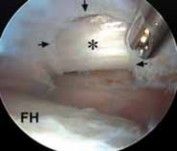

TECH FIG 2•

Arthroscopic view from the peripheral compartment of a right hip.

A.

A window (

arrows

) has been created through the thin medial capsule, exposing the iliopsoas tendon (

) anterior to the femoral head (

FH

).

B.

The tendinous portion is released with a basket.

C.

The final fibers are débrided with a power shaver.

D.

Through the capsular window (

) the tendon has been completely released, preserving the muscular fibers (

). The relation between the capsular window and the acetabular labrum (

AL

) and femoral

D

head (

) is identified. (Courtesy of J. W. Thomas Byrd, MD.)